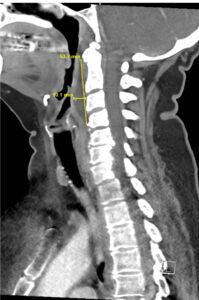

RPA Neck. CT Lateral. Annotated. JETem 2025